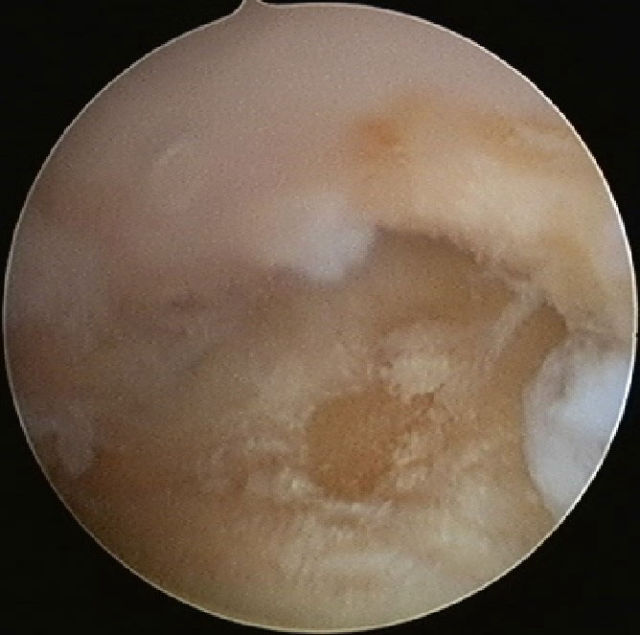

Arthroskopiebefund: Knorpelschaden am Os trapezium

Bei dieser relativ kleinen Operation wird eine 2,5 mm dicke Optik mit Kamera in das Sattelgelenk eingeführt. Man kann dann erkennen, inwieweit der Gelenkknorpel geschädigt ist und wie stark die entzündlichen Veränderungen ausgeprägt sind. Es kann dann mit einer kleinen Fräse oder einem sogenannten „VAPR" eine Reduktion des entzündlichen Gewebes und/oder eine Glättung des Knorpels durchgeführt werden (Gelenktoilette), gleichzeitig können Knorpelanteile, die frei im Gelenk liegen (freie Gelenkkörper) entfernt werden.

Dr. Wittemann ist einer der Pioniere des Sattelgelenksarthroskopie, er hat diesen Eingriff 2004 zum ersten Mal durchgeführt und 2010 die erste Veröffentlichung in deutscher Sprache über diesen Eingriff publiziert. Mittlerweile hat er Sattelgelenkesarthroskopien in deutlich dreistelliger Zahl durchgeführt.